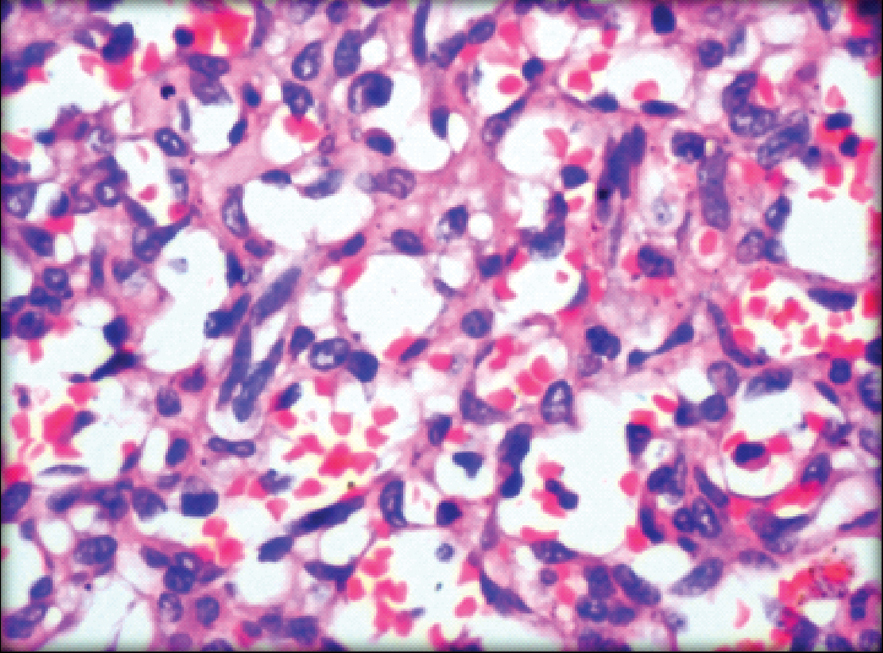

We received a simple mastectomy specimen which measured (13.0x8.0x5.0) cm. Cut surface showed a well circumscribed tumour with areas of haemorrhage measuring (7.5x7.0x5.0) cm. The tumour was 1.5 cm away from the deep resected margin [Table/Fig-2]. On microscopy, sections from the tumour showed anastomosing irregular vascular channels that were dissecting the stroma and were filled with RBC’s. The spaces were lined by epithelioid cells. The cells showed neo lumina formation [Table/Fig-3]. Sheets of tumour cells with high mitotic activity were observed at places. Areas of haemorrhage and ischaemic necrosis were noted [Table/Fig-4]. The nipple areola and deep resected margin were free of tumour. A diagnosis of angiosarcoma was given which was confirmed by Immunohistochemistry (IHC) (CD 34 and factor VIII) [Table/Fig-5].

Anastomosing irregular vascular channels with neo lumina formation (H&E, 20X).